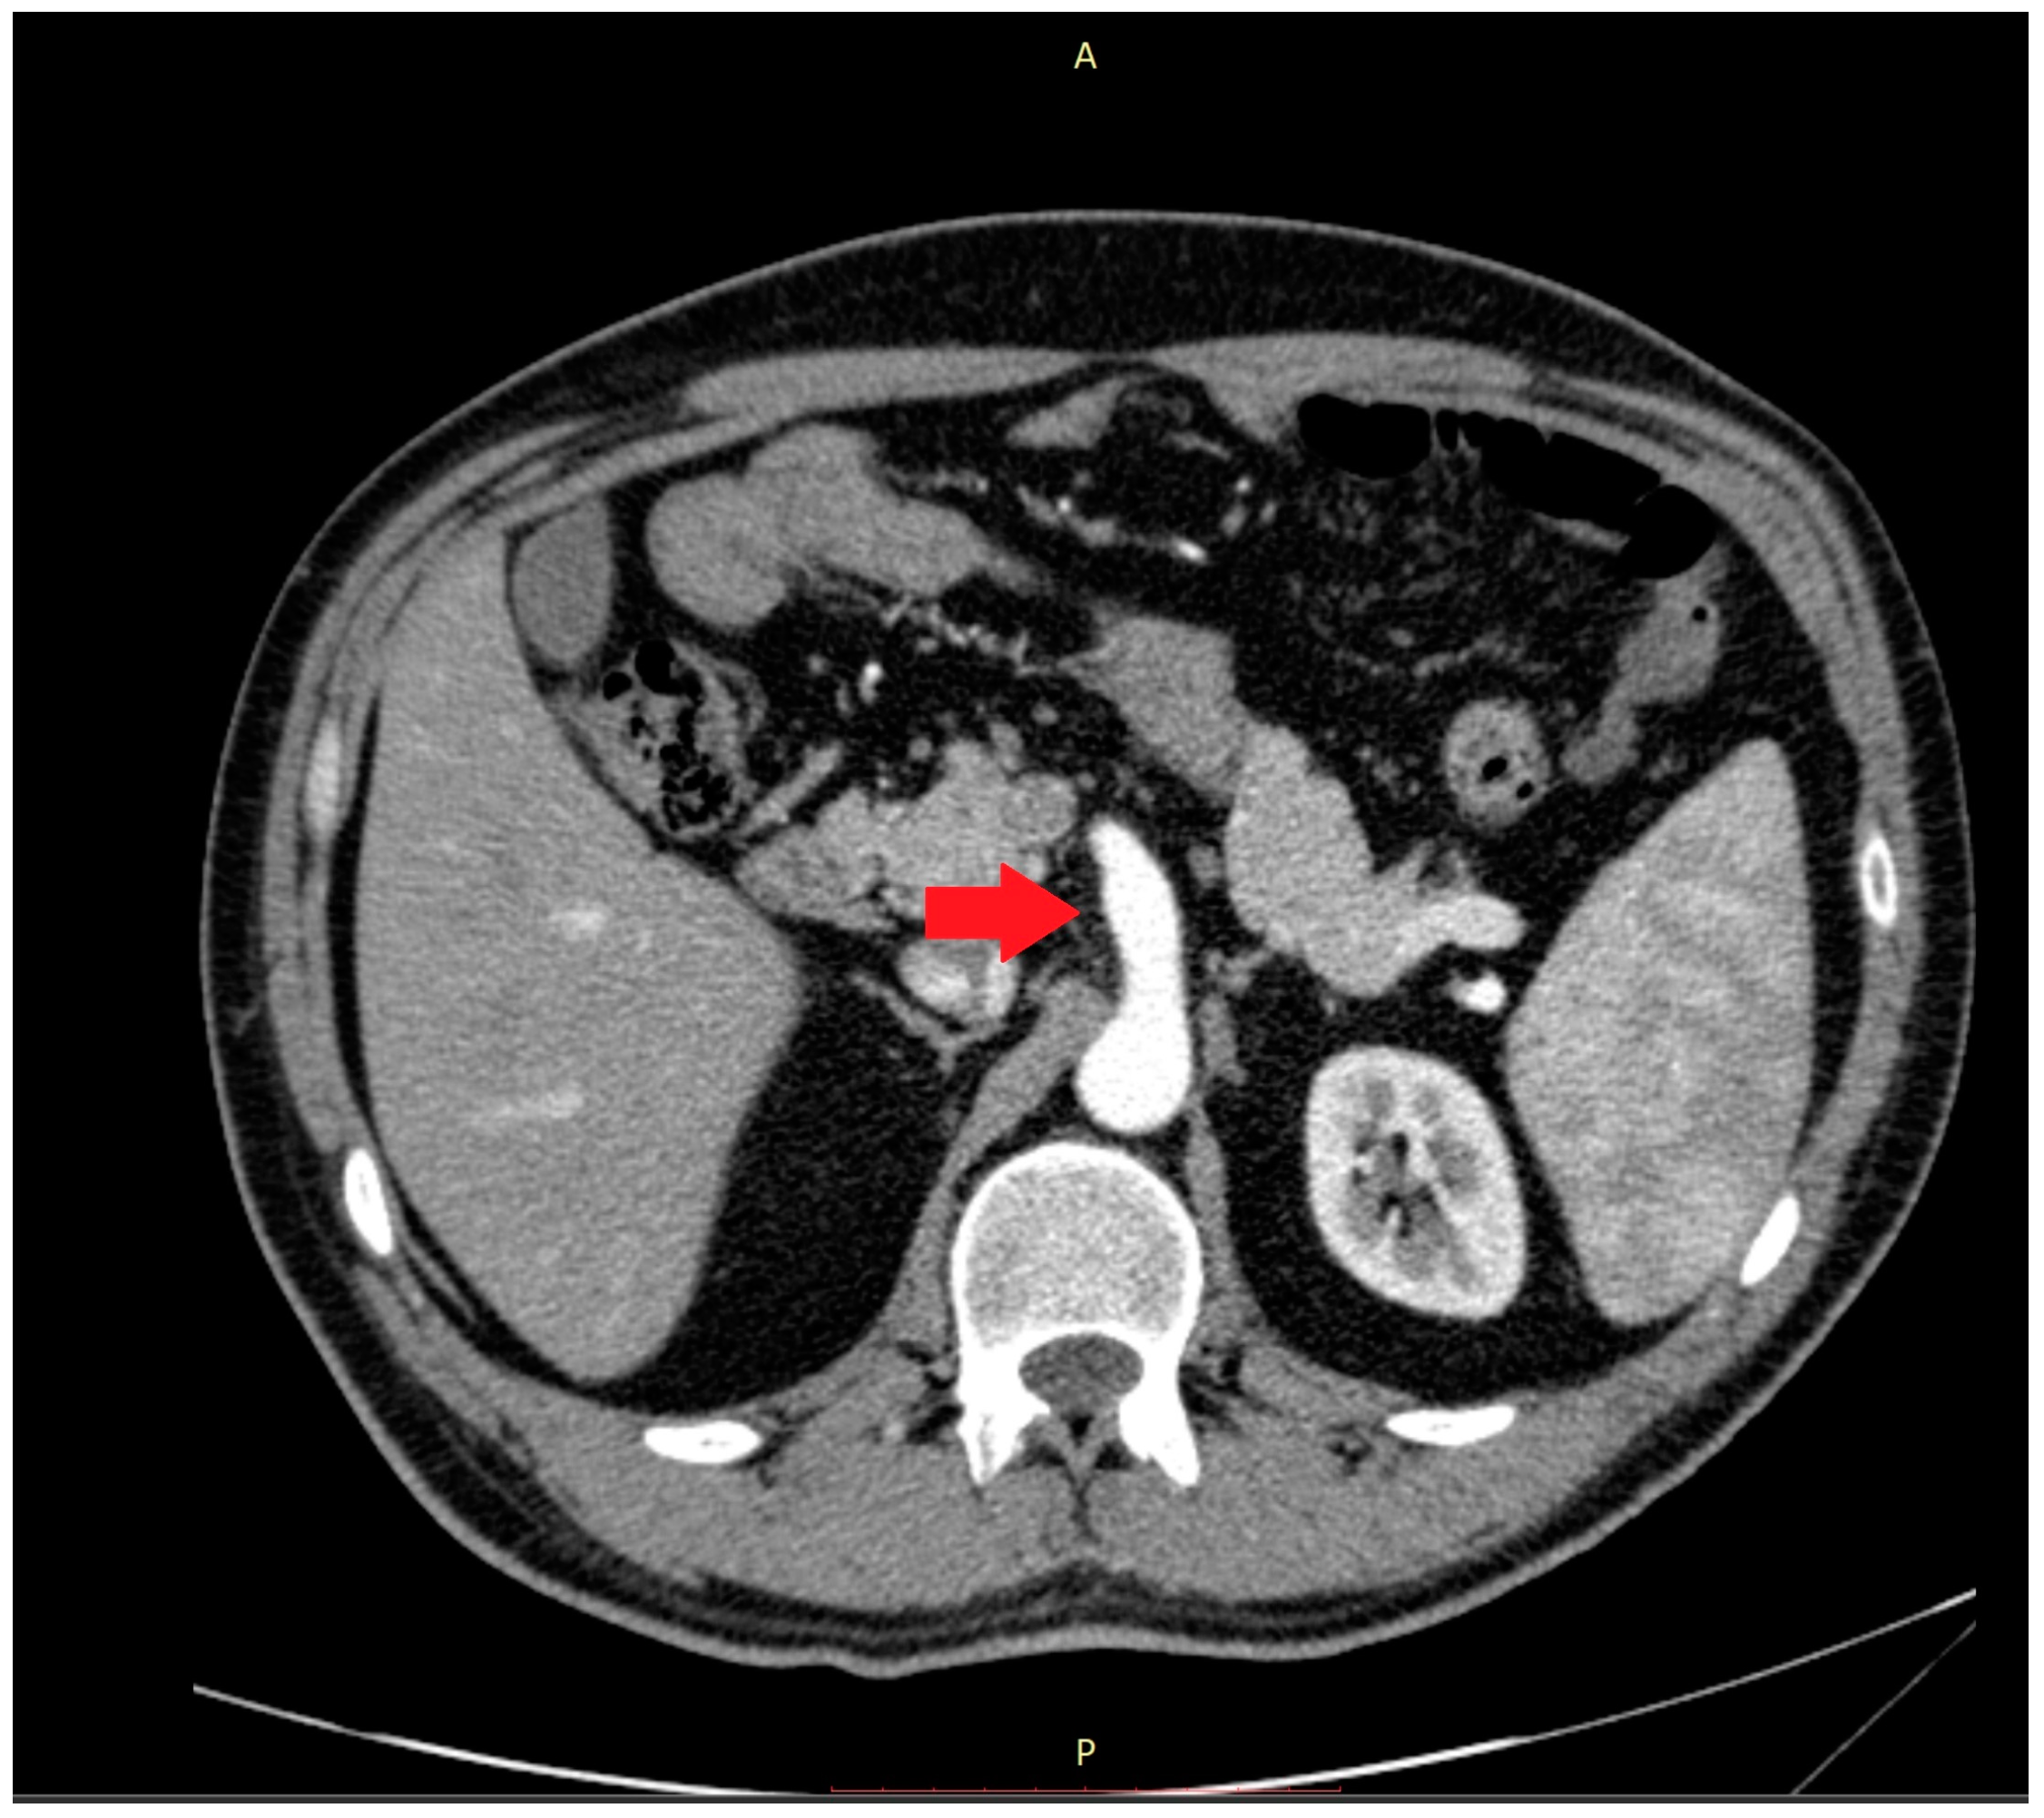

Abnormalities were also present in the CT scan with and without contrast medium (Figure 2 and Figure 3).

Figure 2.

The computer tomography scan confirmed the agenesis of the left hepatic lobe, splenomegaly, and an enlarged celiac-mesenteric trunk (red arrow).